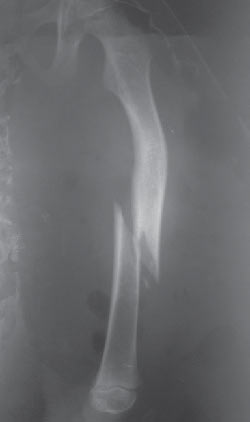

Mujer de 26 años con cuadro clínico consistente en múltiples fracturas a lo largo de su vida con inicio a los 17 meses de edad con fractura de fémur izquierdo y refractura del mismo a los 4 años de edad (figura 1), posteriormente a los 9 años fractura condílea derecha y a los 10 años fractura radial y cubital izquierda (figura 2), todas con traumas mínimos.

|

| Figura 1. Fractura de fémur izquierdo |